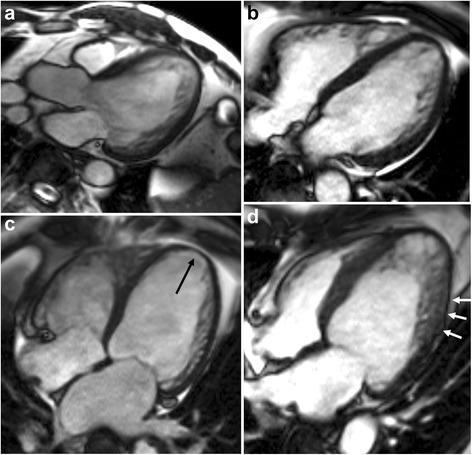

METHODS

This retrospective study included 145 subjects with mild to severe trabeculation of the left ventricle myocardium [24 patients with isolated LVNC, 33 patients with non-isolated LVNC, 30 patients with dilated cardiomyopathy (DCM) with non-compaction (DCMNC), 27 patients with DCM, and 31 healthy control subjects with mild trabeculation]. The left ventricular (LV) ejection fraction, global LV myocardial volume, trabeculated LV myocardial volume, and number of segments with late gadolinium enhancement were measured. In addition, the most prominent non-compacted (NC), compacted (C), normal mid-septum, normal mid-lateral wall, and apical trabeculation thicknesses on the end-diastolic frames of the long-axis slices were measured.

方法

本回顾性研究纳入了145例左心室心肌小梁化程度从轻到重的受试者[24例孤立性LVNC患者、33例非孤立性LVNC患者、30例伴有心肌致密化不全的扩张型心肌病(DCM)患者、27例DCM患者以及31例心肌小梁化程度较轻的健康对照者]。测量左心室(LV)射血分数、左心室整体心肌体积、小梁化左心室心肌体积以及延迟钆增强节段数。此外,还测量了长轴切片舒张末期帧上最突出的非致密化(NC)、致密化(C)、正常室间隔中部、正常室侧壁中部以及心尖小梁厚度。